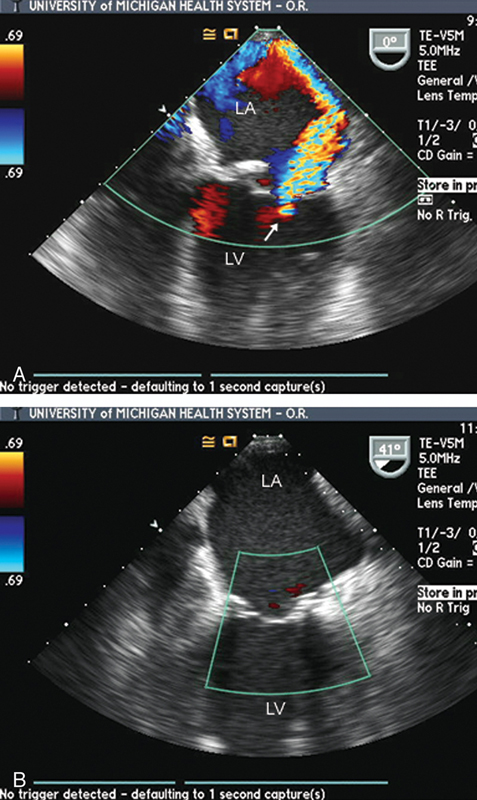

فحوصات تشخيصية لبعض امراض القلب والشرايين التاجية